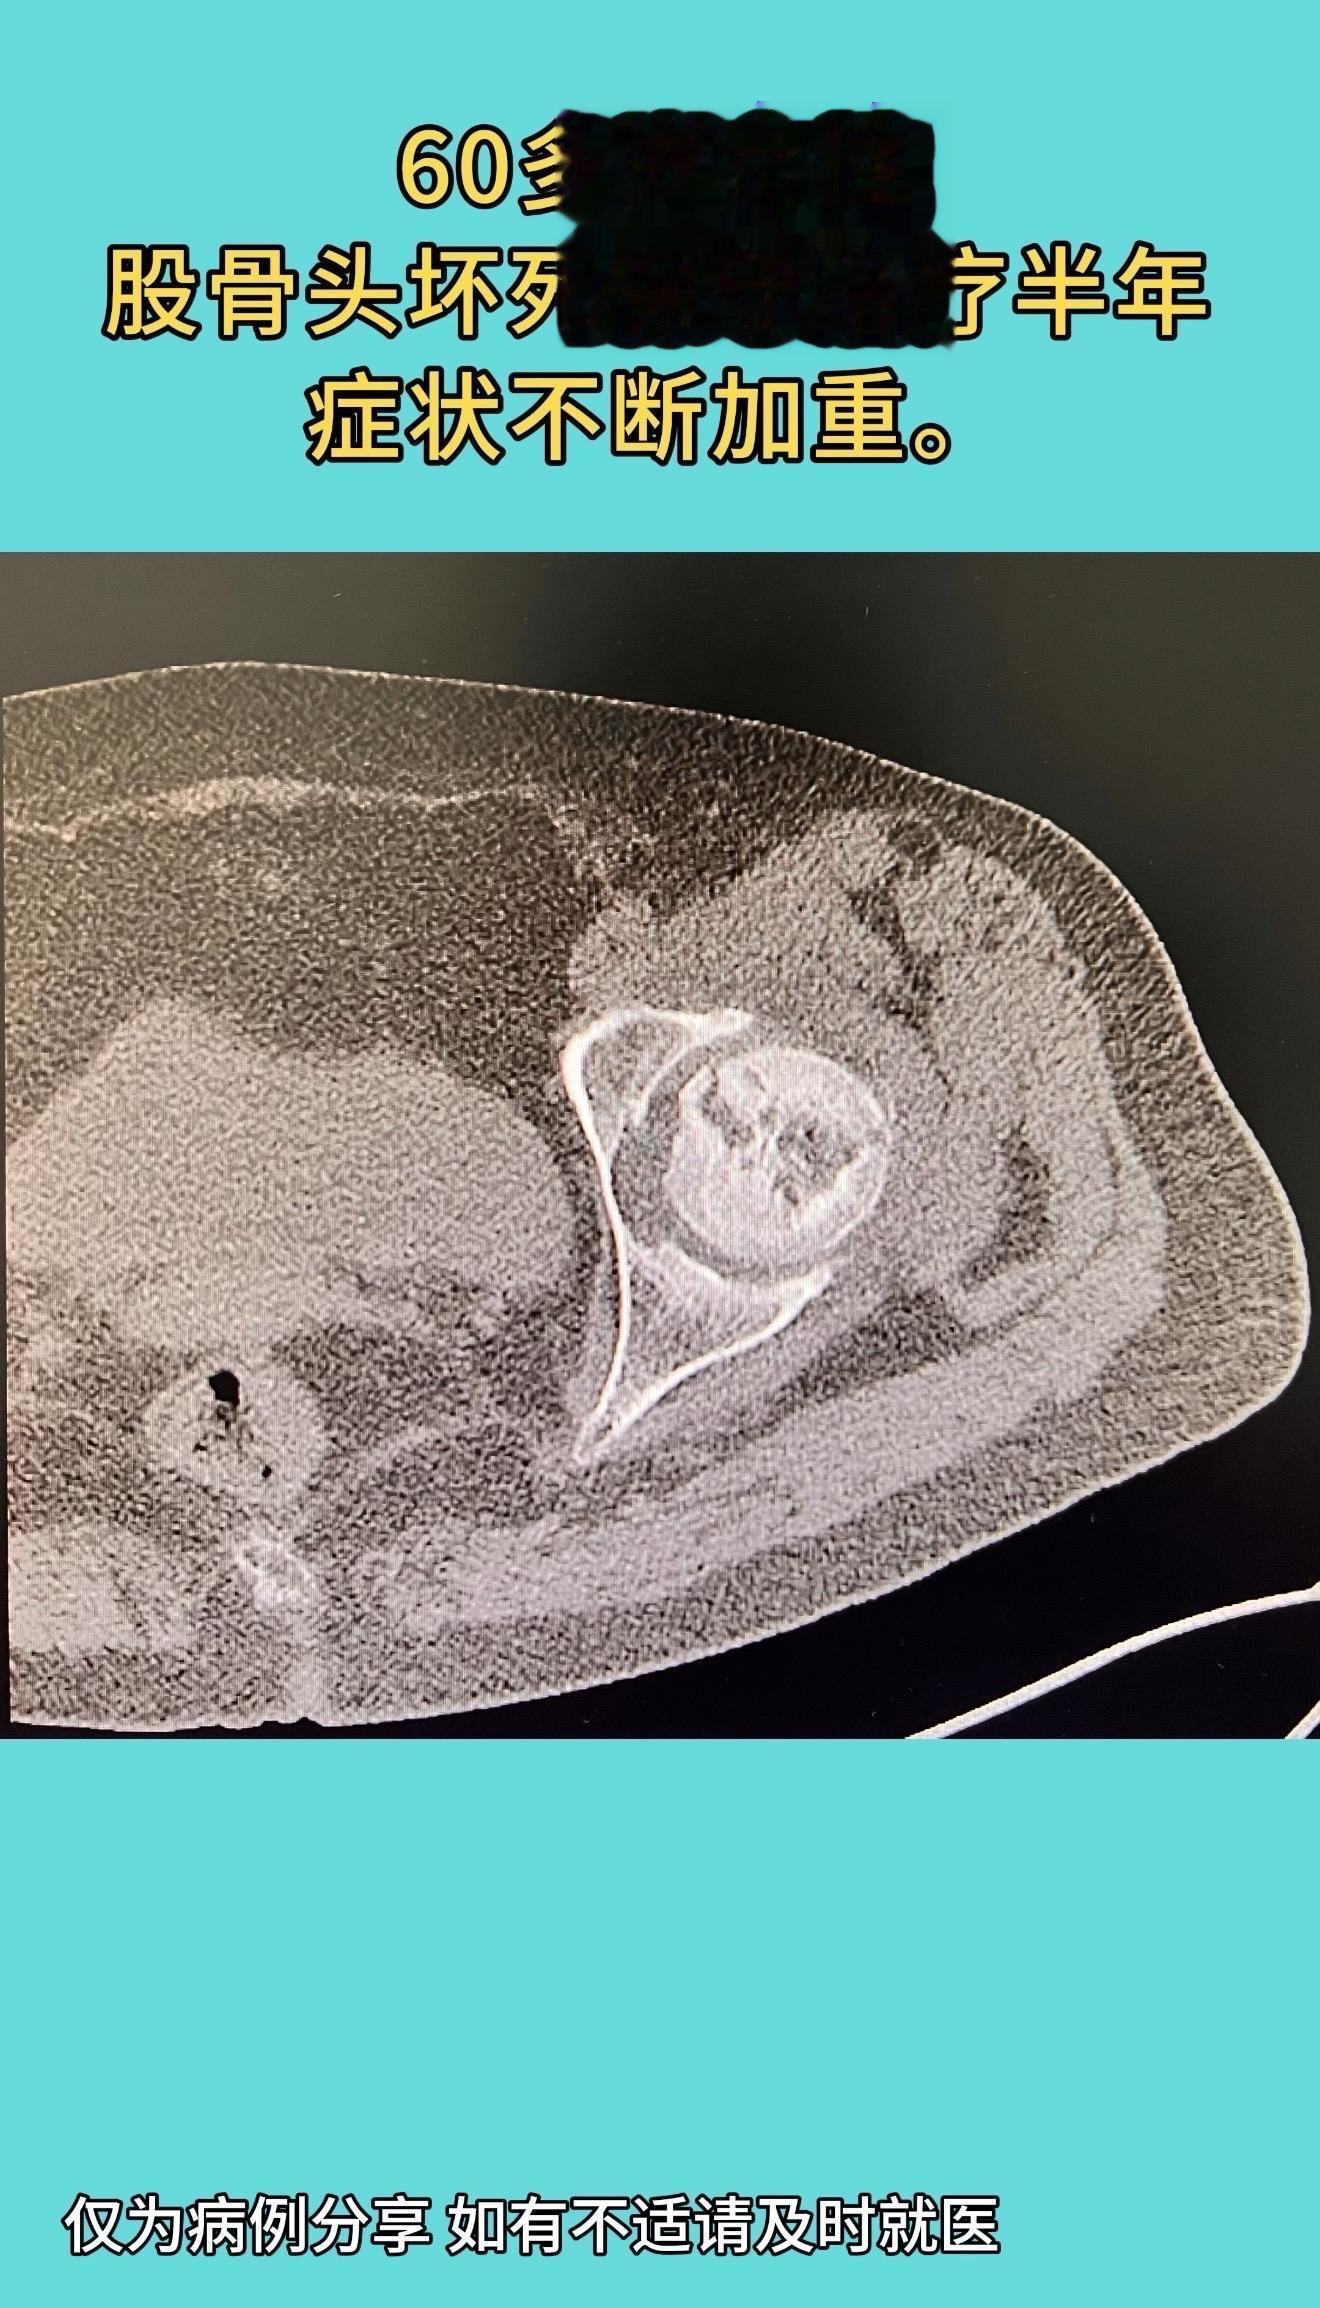

国内顶尖专家做的一例全髋置换手术:片子漂亮的像一件艺术品,术后症状缓解,双下肢等长,活动度佳。60多岁女性,股骨头坏死保守治疗半年,症状不断加重。